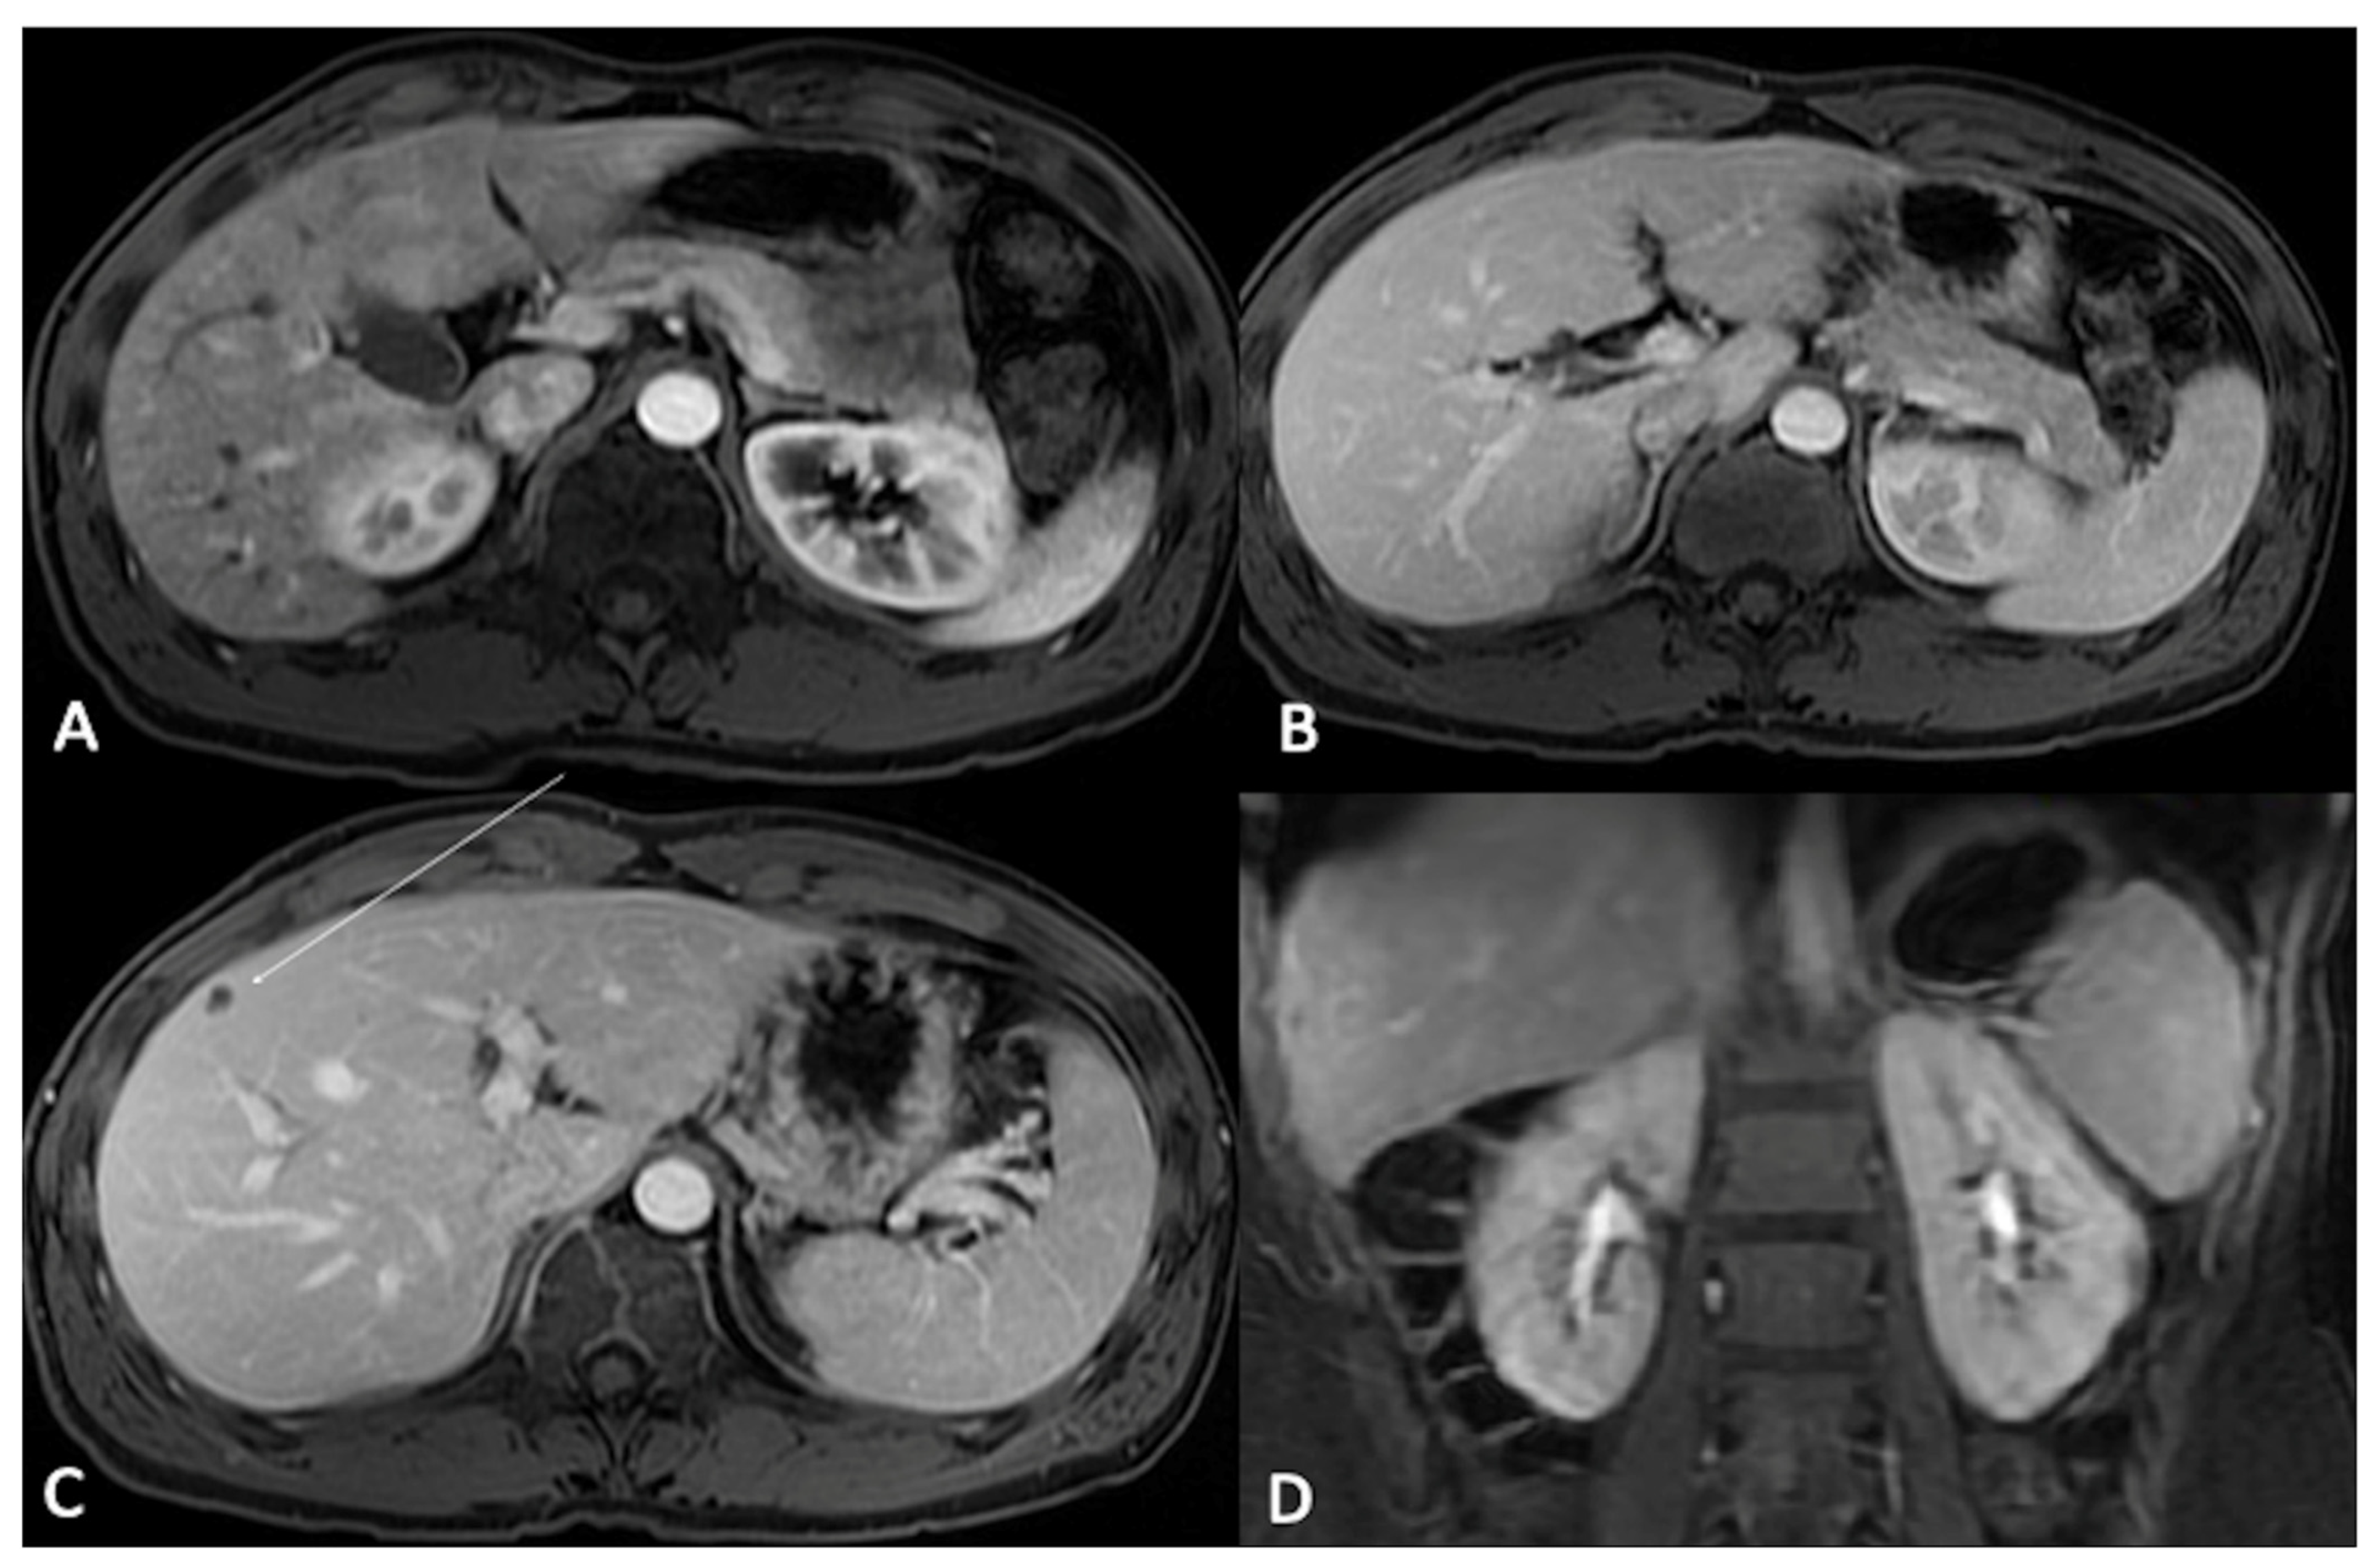

Figure 4. T1-weighted Liver Acquisition Volume Acceleration (LAVA) axial (AC) and coronal (D) images after ECSA intravenous administration in the different phases of a complete dynamic post-contrast RM study. (A) The early arterial phase shows the arterial structures, generally represented by arterial vascular structures; (B) the late arterial phase shows the enhancement of hypervascular tissues such as abdominal parenchymas: please note that it is possible to evaluate pancreas, spleen, or renal cortex. (C) In the venous phase, the liver enhancement is optimally visualized: this phase represent the best moment to evaluate the liver parenchyma and focal lesions, as demonstrated by the clear visualization of a small hypointense focality in the subcapsular plane (arrow). (D) In the delayed/equilibrium phase, interstitial and extracellular spaces are finally enhanced, and it is possible to evaluate urinary excretion of contrast and opacification of renal collecting system.

• When using ECSAs, in the early arterial phase, arterial structures are enhanced, while in the late arterial phase, hypervascular tissues (including normal parenchymas such as the pancreas, spleen, or renal cortex) are visible. The venous phase allows for the best liver enhancement. In the delayed/equilibrium phase (occurring between 3 and 5 min from contrast injection), interstitial and extracellular spaces are finally enhanced (Figure 4).